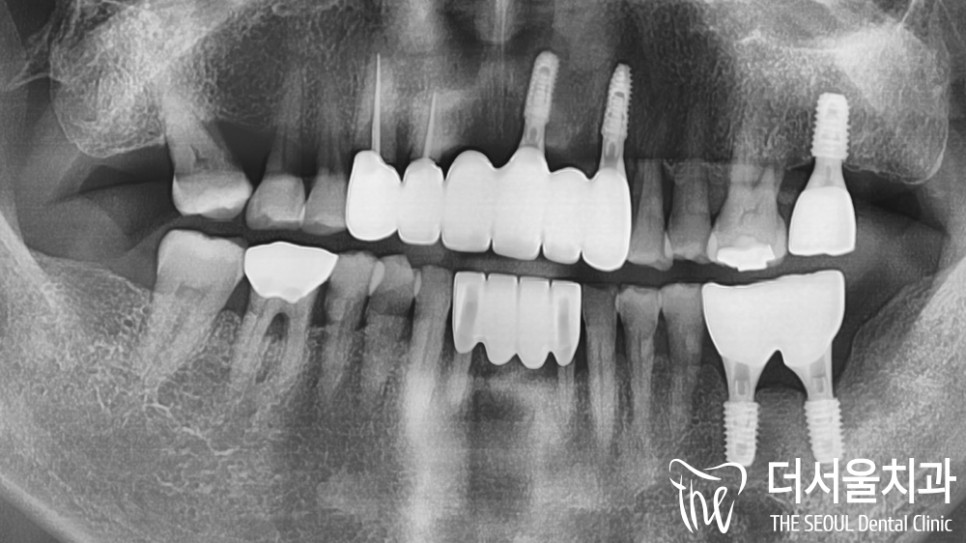

우선 환자의 초진 사진을 살펴볼까요?

음.. 한눈에 봐도 심하게 손상된 치아를

육안관찰에서 확인할 수 있었습니다.

이곳은 이전에 치료를 받았던 곳인데요.

오래된 것도 그렇고,

제대로 된 관리를 하지 못해

외관은 물론이며 치조골까지 소실이 되어있네요.

다행히 이전에 올려드렸던

어금니는 튼튼하게 심어져 있었습니다 🙂

위쪽과 더불어 아래쪽에도 문제가 있었습니다.

치경부 마모는 물론이며

잇몸이 내려앉아 있었는데요.

파노라마로 살펴보니

이곳에서도 심한 염증이 관찰되었습니다.